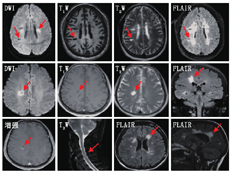

(1)腔隙性脑梗死:病灶直径3~15 mm,呈边缘清晰的圆形、裂隙状或椭圆形,MRI/T1WI呈低信号而T2WI呈高信号;急性期的DWI为高信号。陈旧性腔隙性脑梗死:在FLAIR上病灶呈低信号,周围有胶质增生的高信号。病灶主要分布于基底节、丘脑、内囊、豆状核和尾状核、脑干等脑穿支动脉供血区域。(2)多发性硬化:脑和脊髓均可有病灶,为多病灶,呈非对称性,通常有相对固定的分布模式及形态;病灶与侧脑室垂直分布;在T1WI为低信号,T2WI为高信号(煎蛋状、云雾状),FLAIR为高信号,急性期DWI呈高信号,增强后呈C形或开环状强化。

DWI:弥散加权成像;FLAIR:液体衰减反转恢复序列